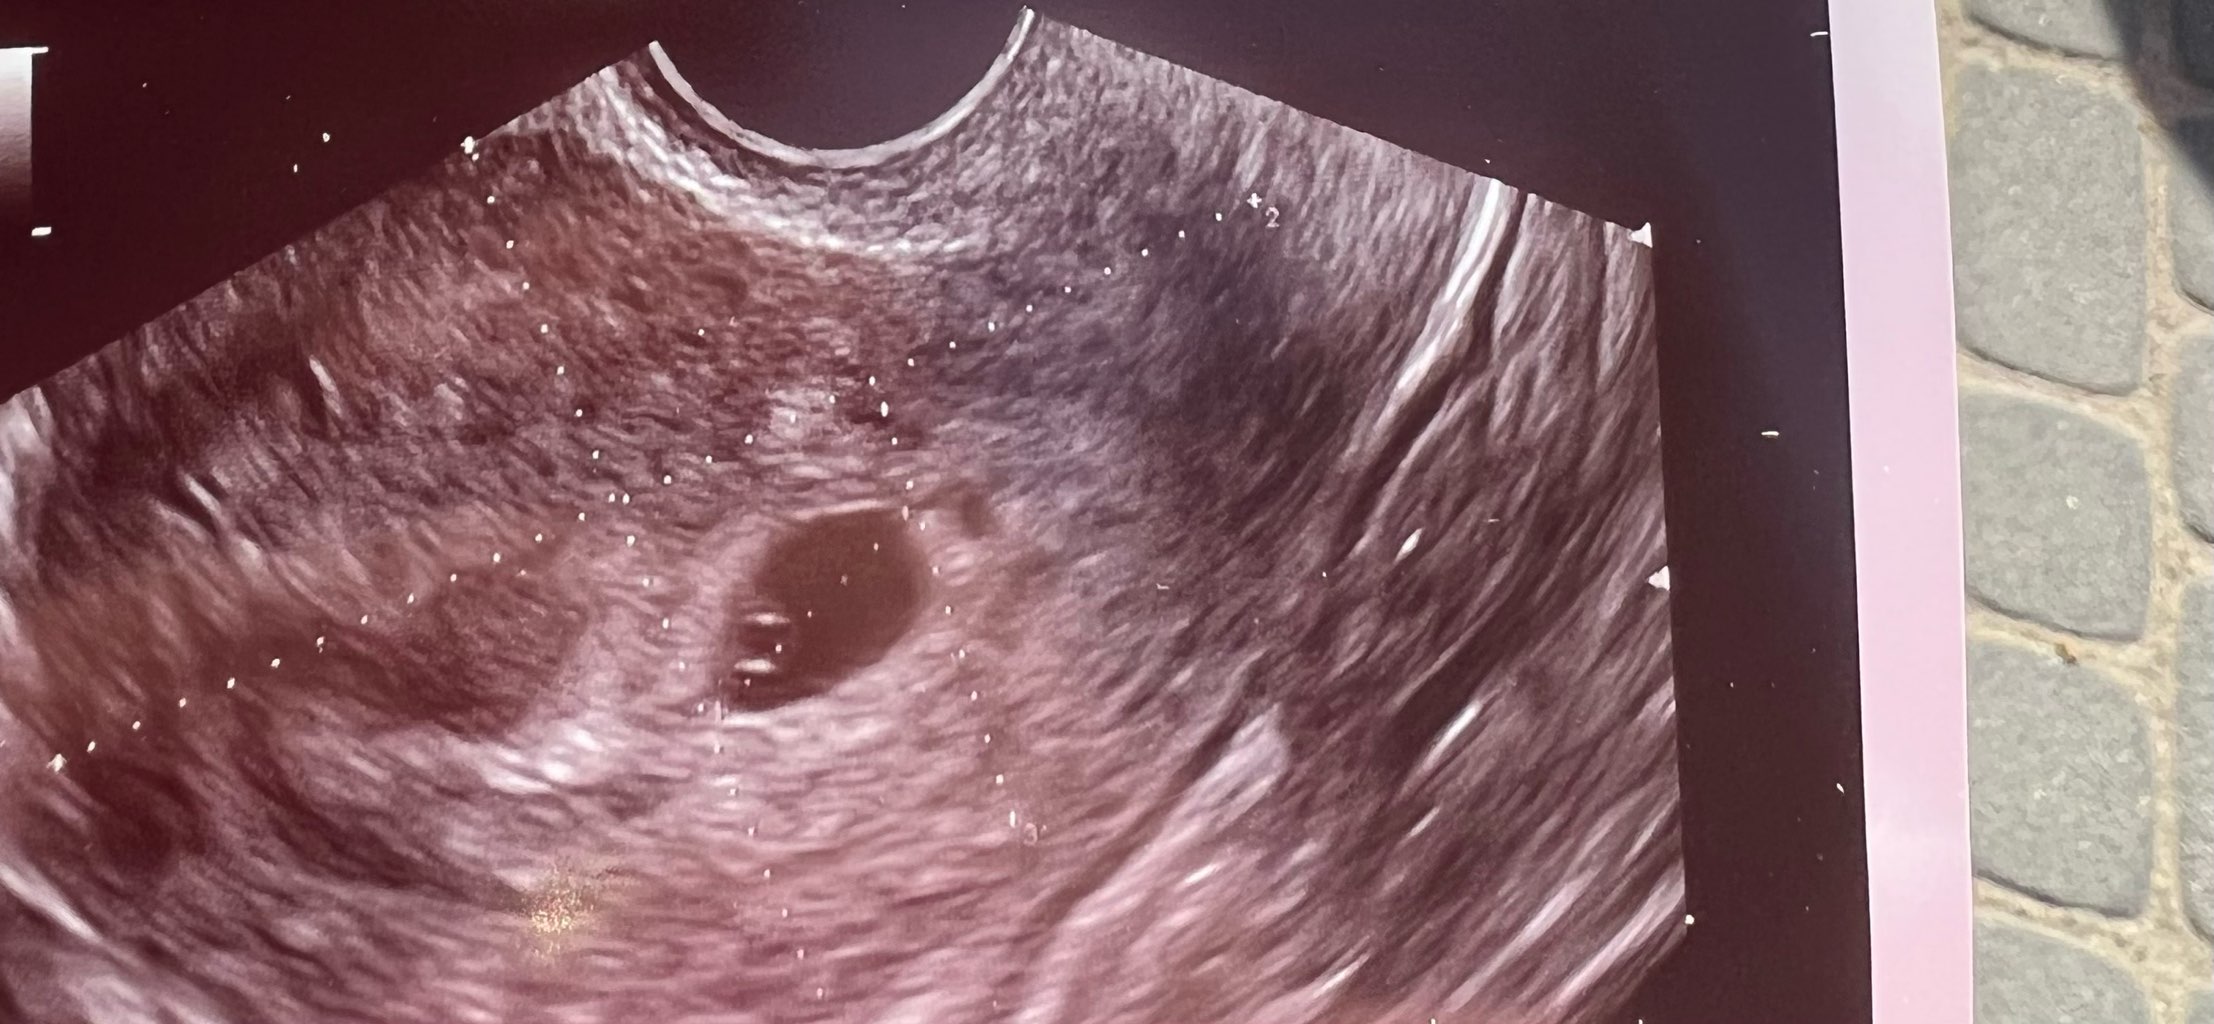

W zeszłym tygodniu robiłam bete i miała 445, dzisiaj byłam u ginekologa, zrobił usg powiedział że jest widoczny pęcherzyk ciążowy, ale nic więcej. Wielkość pęcherzyk to 0,84 cm. Nie mówił który to tydzień, myślę że 5/6 tydzień.

Martwi mnie jednak brak ciałka żółtego No i zarodka również. Następnego usg za dwa tygodnie. Jest się czym martwić?

spokojnie, przy takiej wielkości pęcherzyka ma prawo nie być. Patrz jaki mój był mały przy 1,25